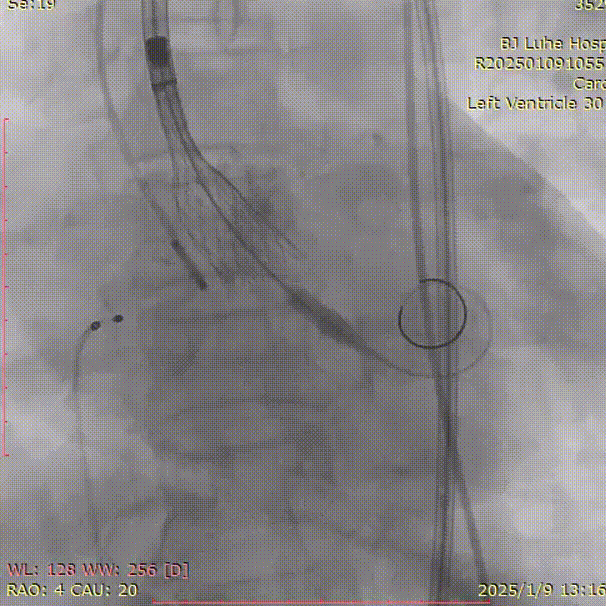

术中影像

右冠造影

左冠造影

主动脉根部造影

初始定位

瓣膜位置偏浅

调整植入深度